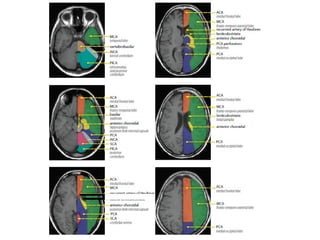

b) Cerebral Arterial Territory :

1-Posterior Inferior Cerebellar Artery

2-Superior Cerebellar Artery

3-Branches from vertebral and basilar artery

4-Anterior Choroidal artery

5-Lenticulostriate arteries

6-Anterior cerebral artery

7-Middle cerebral artery

8-Posterior cerebral artery

1-Posterior Inferior Cerebellar Artery (PICA in blue)

-The PICA territory is on the inferior occipital

surface of the cerebellum and is in equilibrium

with the territory of the AICA in purple which

is on the lateral side

-The larger the PICA territory , the smaller the

AICA and vice versa

2-Superior Cerebellar Artery (SCA in grey)

-The SCA territory is in the superior and tentorial

surface of the cerebellum

-These branches supply the medulla oblongata

(in blue) and the pons (in green)

4-Anterior Choroidal artery (AchA in blue)

-The AChA originates from the posterior wall of

the ICA between origin of PCOM which is 2-5 mm

proximally and the internal carotid termination,

which is 2-5 mm distal to the AChA

The territory of the AChA is part of the hippocampus ,

the posterior limb of the internal capsule , optic tract

, mid brain , lateral geniculate nucleus and choroid

plexus of the anterior part of the temporal horns of

the lateral ventricles

-It has 2 segments , cisternal and intraventricular

-The lateral LSA (in orange) are deep penetrating

arteries of the middle cerebral artery (MCA)

-Their territory includes most of the basal ganglia

-The medial LSA (indicated in dark red) arise from

the ACA (usually the A1 segment)

-Heubner's artery is the largest of the medial

lenticulostriate arteries and supplies the

anteromedial part of the head of the caudate and

anteroinferior internal capsule

-The territory of the lateral lenticulostriate

perforating arteries of the MCA is indicated

with a different color from the rest of the

territory of the MCA because it is a well-

defined area supplied by penetrating branches

which may be involved or spared in infarcts

separately from the main cortical territory of

the MCA

6-Anterior Cerebral Artery (ACA in red)

-The ACA supplies the medial part of the frontal

and the parietal lobe and the anterior portion

of the corpus callosum , basal ganglia and

internal capsule

-A1 segment : from origin to ACOM and gives rise

to medial lenticulostriate arteries (inferior parts

of the head of the caudate and the anterior limb

of the internal capsule)

-A2 segment : from ACOM to bifurcation of

pericallosal and callosomarginal arteries

-A3 segment : major branches (medial portions of

frontal lobes , superior medial part of parietal

lobes , anterior part of the corpus callosum)

7-Middle cerebral artery (MCA in yellow)

-The cortical branches of the MCA supply the

lateral surface of the hemisphere except for

the medial part of the frontal and the parietal

lobe (anterior cerebral artery) and the inferior

part of the temporal lobe (PCA)

-The deep penetrating LSA branches are

discussed before

8-Posterior cerebral artery (PCA in green)

-P1 extends from origin of the PCA to the posterior

communicating artery contributing to the circle

of Willis

-Posterior thalamoperforating arteries branch off

the P1 segment and supply blood to the midbrain

and thalamus

-Cortical branches of the PCA supply the

inferomedial part of the temporal lobe , occipital

pole , visual cortex and splenium of the corpus

callosum

-Deep or proximal PCA strokes cause ischemia in

the thalamus and / or midbrain as well as in

the cortex

-Superficial or distal PCA infarctions involve only

cortical structures

-Only about 5% of ischemic strokes involve the

PCA or its branches